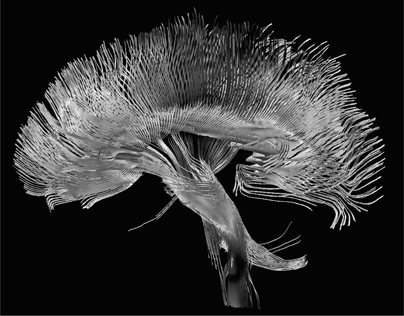

由于不同的化学元素对不同频率的射频有响应,你可以改变射频脉冲的频率,从而识别身体的不同元素。如前所述,fMRI机器专注于血液中的氧原子以测量血流,但MRI机器也可以调谐以识别其他原子。就在过去十年中,引入了一种称为”扩散张量成像”MRI的新形式,它检测大脑中水的流动。由于水沿着大脑的神经通路流动,DTI产生美丽的图像,类似于花园中生长的藤蔓网络。科学家现在可以立即确定大脑的某些部分如何与其他部分连接。

图5. 在上方,我们看到功能性MRI机器拍摄的图像,显示了高精神活动区域。在下方图像中,我们看到扩散MRI机器创建的花朵状图案,它可以追踪大脑的神经通路和连接。(illustration credit 1.5a)